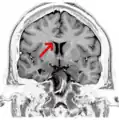

MRI of corpus callosum and its named parts

Corpus callosum